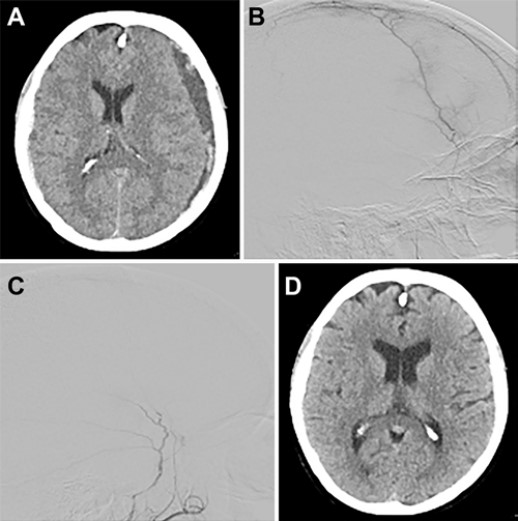

表1. 121例MMA栓塞术治疗NASH的患者基线数据表2. 121例MMA栓塞治疗NASH的临床及影像学因素分析151例MMA栓塞术,148例成功,3例失败发生在老年组(表3)。老年组和高龄组分别有46%(40/87)和61%(39/64)患者接受了前期治疗。老年组中,主要是开颅手术(50%,16/32)或钻孔引流术(47%,15/32)。在高龄组中,开颅手术6例(29%),钻孔11例。预防性治疗在老年组和高龄组分别为15%(13/87)和6%(4/64)。每组80%以上采用经股动脉途径,两组约有1/2病例使用全麻(表3)。两组平均手术时间几乎相同,没有显著差异。两组栓塞剂的选择相似,最常见的是颗粒加弹簧圈(老年组51%,高龄组44%)。近2/3病例使用栓塞微粒(Merit Medical),最常见的是100-300µm或300-500µm范围;而其余1/3使用聚乙烯醇颗粒,在150-250-µm范围或250-355-µm范围。在液体栓塞中,90%的病例使用Onyx。表3. 121例MMA栓塞术治疗NASH的治疗信息在6周随访中,硬膜下血肿最大宽度在组间无显著差异(老年组和高龄组为10.9 mm vs 9.31mm,p=0.28)(表4)。在90天随访中,两组之间的NASH宽度相似(4.66 vs 6.13mm,p=0.22)。在6周随访中,高龄组的血肿宽度明显减少(p=0.002)。在6周的随访中,大多数患者的NASH改善;老年组和中老年组NASH稳定或改善率分别为91%(73/80)和98%(57/58)。同样,在大多数老年人(61%)和高龄老年人(64%)中观察到>50%的改善,而两组分别观察到24%和17%的完全缓解,典型病例见图1。NASH恶化较少见(老年组和高龄组分别为8.8%和1.7%)。表4. 121例接受MMA栓塞术治疗NASH的疗效分析图1. 左侧NASH采用MMA栓塞治疗的病例。67岁女性患者,因肺栓塞服用香豆素类治疗,出现头痛。CT扫描轴位相(A)上,血肿厚度为11.0毫米。采用100-300µm栓塞微粒(Merit-Medical)对MMA的前、中支进行栓塞(B和C)。在90天的随访CT显示,NASH完全消失(D)。